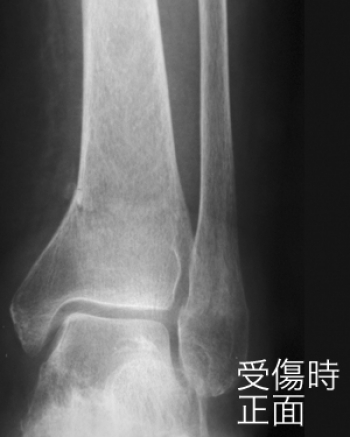

今日、ご紹介するのは、下腿遠位端部骨折についてご紹介していきます。

下腿骨遠位端部骨折

足関節部の骨折は、とくにスポーツ外傷で多発します。

解剖学的状態への回復に失敗すると、足関節の動揺性や、変形性関節症を残し、機能障害を生ずることもある。

外転型骨折

もっともみられる果部骨折は、足関節の外転強制によって距骨が斜位となり、足関節内側の靭帯が緊張して断裂し、または靭帯が断裂しないで内果の剥離骨折を生じる。

これによって距骨はさらに外転して、外果の内面に衝突し、体重による屈折力も加わって、腓骨は外果の上方で骨折する。

そのとき、脛腓靭帯が断裂して両骨が離開し、その間に距骨がはまり込むこともある。あるいは、その靭帯が断裂せず、靭帯の脛骨付着部が剥離骨折を起こすこともある。